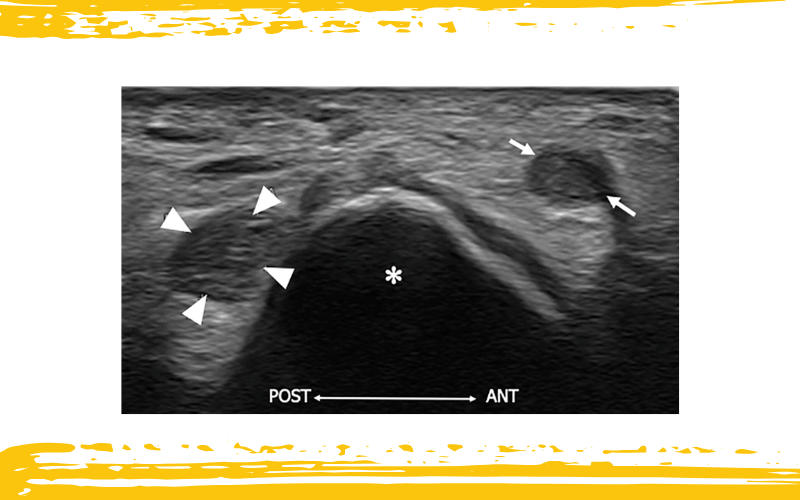

La imagen ecográfica muestra un nervio cubital aumentado de tamaño (cabezas de flecha blancas) con pérdida de la ecotextura fascicular, consecuencia de una neuropatía compresiva de larga evolución.

Tras la liberación del túnel cubital, se observa la rama posterior aumentada del MCNF, visible inmediatamente anterior al epicóndilo medial (asterisco blanco), resultado de la formación de un neuroma en continuidad.

La presencia de numerosas ramas terminales del MCNF y su trayectoria impredecible en la región medial del codo explican por qué este nervio puede suponer una complicación durante la cirugía del túnel cubital.